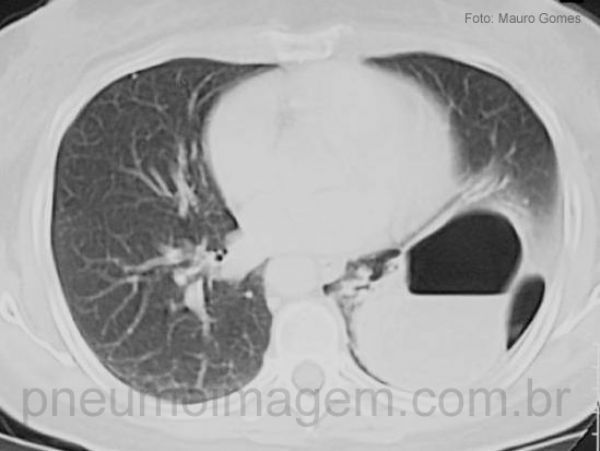

No corte tomográfico observa-se hérnia intratorácica do estômago e cólon. A grande maioria das rupturas diafragmáticas por trauma contuso (80%-90%) ocorre do lado esquerdo. Os sinais e sintomas, inclusive radiológicos, não são específicos e a maioria das lesões não é diagnosticada prontamente. Assim, a ruptura diafragmática pode não ser reconhecida e tratada imediatamente, resultando em herniação progressiva das estruturas abdominais para o interior do tórax que pode levar anos e determinar estrangulamento visceral, com morbidade alta. As lesões diafragmáticas à direita, embora menos freqüentes, estão associadas a lesões mais graves e maior instabilidade hemodinâmica.

In this section we can see intrathoracic hernia of the stomach and colon. The vast majority of diaphragmatic ruptures due to blunt trauma (80% -90%) occur on the left side. Signs and symptoms, including radiologic, are not specific and most of the lesions are not diagnosed promptly. Thus, diaphragmatic rupture may not be recognized and treated immediately, resulting in progressive herniation of abdominal structures into the chest that may take years and determine visceral strangulation with high morbidity. Right diaphragmatic lesions, although less frequent, are associated with more severe lesions and greater hemodynamic instability.